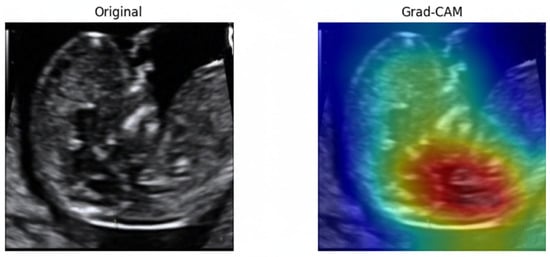

To examine the model’s decision-making process, Gradient-weighted Class Activation Mapping (Grad-CAM) [67]. As illustrated in Figure 25, the model consistently directed its attention to the fetal nuchal region—the clinically relevant anatomical structure used for NT evaluation. Warmer colors (red, yellow) indicate regions contributing most strongly to the classification output.

Figure 25.

Original ultrasound image and corresponding Grad-CAM heatmap.

The focused activation over the NT space confirms that the model learned meaningful, physiologically aligned representations rather than relying on irrelevant background textures. This explainability further supports clinical trustworthiness and transparency in automated NT image assessment.

In the first stage, image-quality assessment using DenseNet121 achieved superior performance compared to other widely used convolutional neural network architectures, including VGG, ResNet, EfficientNet, and Inception variants. The achieved accuracy of 0.94 and AUC of 0.986 demonstrate that DenseNet121 effectively discriminates between standard and non-standard NT ultrasound images, even when trained on a relatively limited dataset. This result is consistent with previous findings indicating that dense feature reuse improves performance in medical imaging tasks with limited data availability. Importantly, Grad-CAM visualizations confirmed that the model consistently attended to anatomically relevant regions around the fetal neck rather than irrelevant background structures, supporting the clinical plausibility of the learned representations.